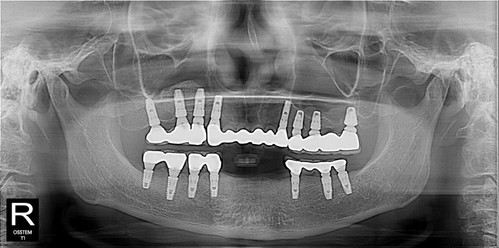

뽑고 임플란트가 최선일 것 같습니다..

이제 앞니 보철 할 때까지 기다리시기만하면 됩니다.~